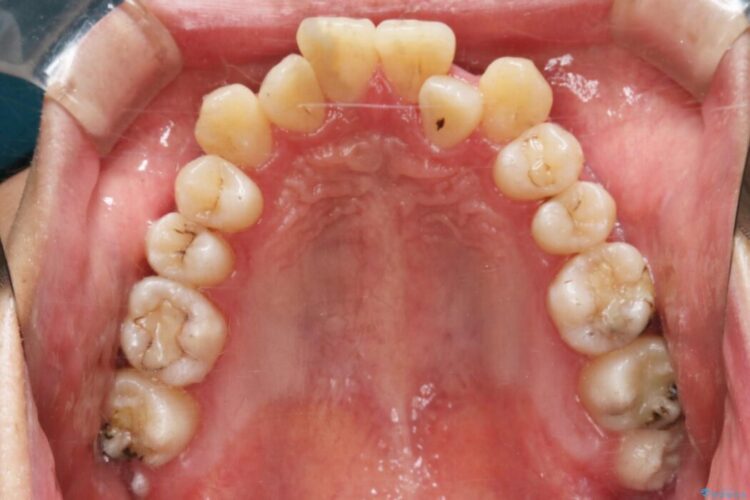

上顎歯列弓のガタガタを治療したいとのことで来院されました。

非抜歯での矯正治療ではスペースの確保が必要となります。

・歯の遠心移動

・歯列弓の拡大

・IPR(歯の側面を少し削る)

本症例では上記3つの方法を複合的に組み合わせた治療を行いました。